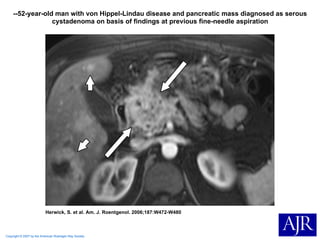

Copyright © 2007 by the American Roentgen Ray Society Herwick, S. et al. Am. J. Roentgenol. 2006;187:W472-W480 --52-year-old man with von Hippel-Lindau disease and pancreatic mass diagnosed as serous cystadenoma on basis of findings at previous fine-needle aspiration

Copyright © 2007by the American Roentgen Ray Society Herwick, S. et al. Am. J. Roentgenol. 2006;187:W472-W480 --52-year-old man with von Hippel-Lindau disease and pancreatic mass diagnosed as serous cystadenoma on basis of findings at previous fine-needle aspiration